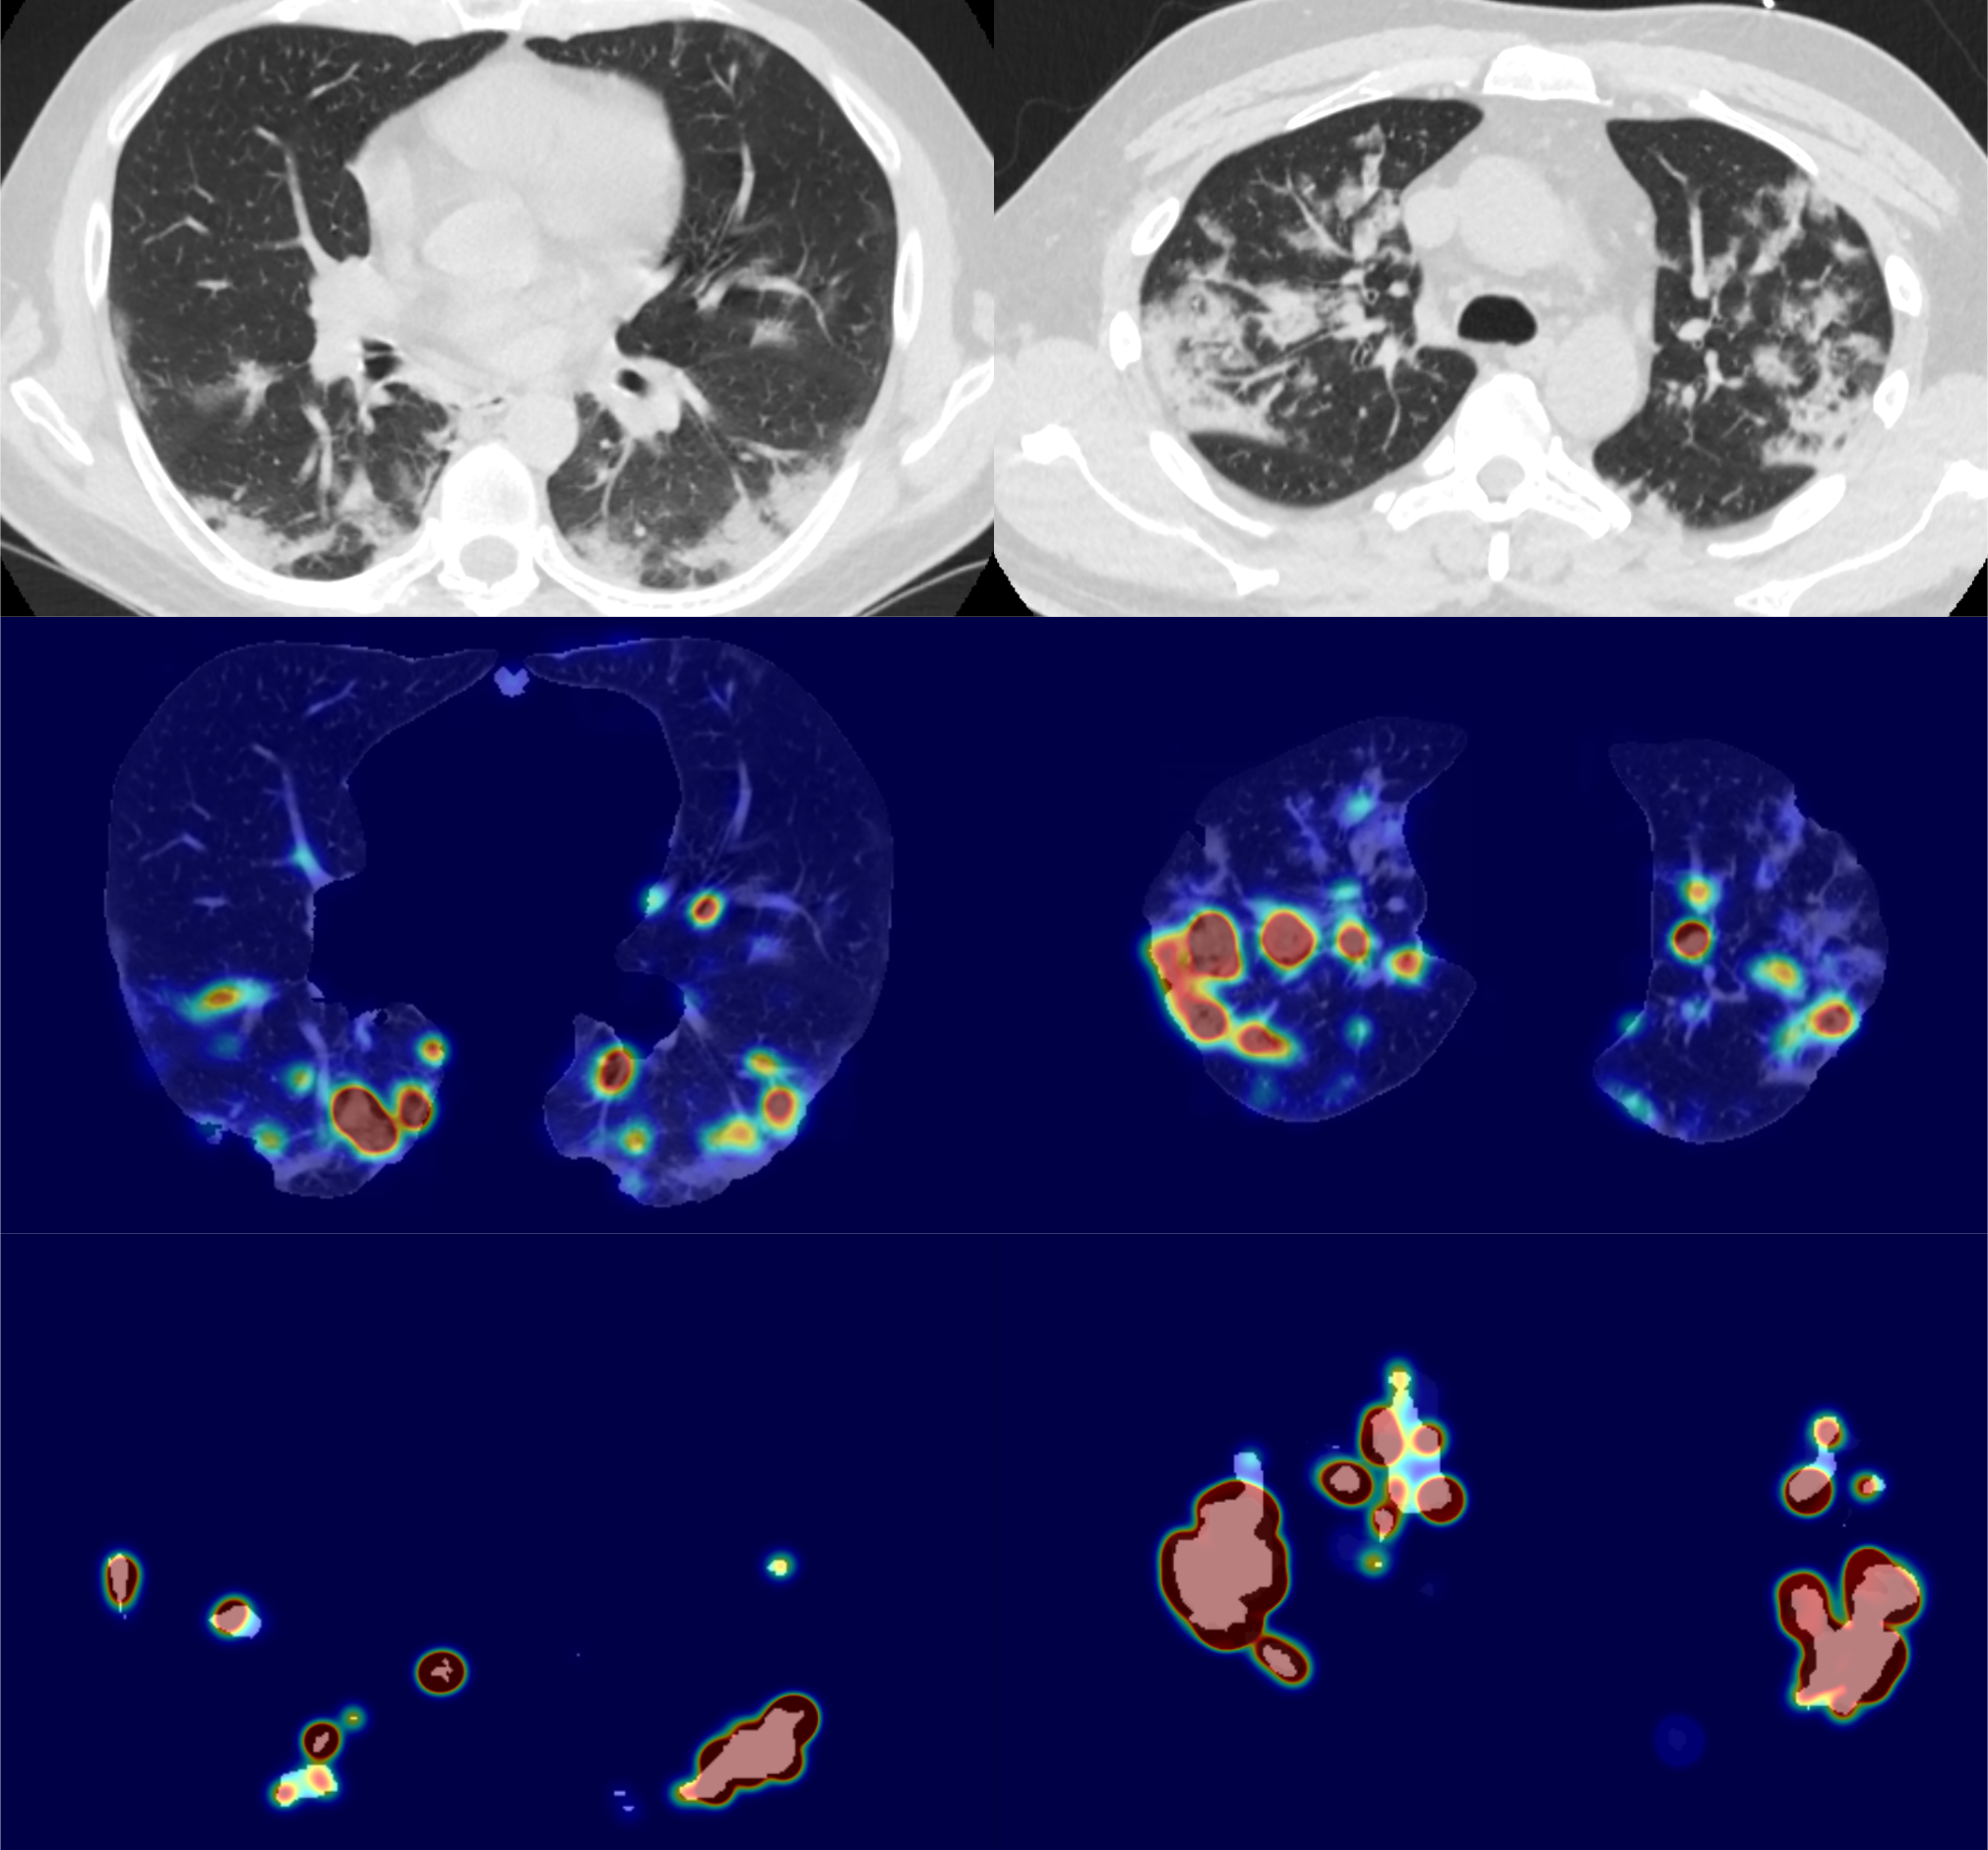

5.4 Visual explanations

In Figure 8, we provide 4 examples of relevance heatmaps for correctly-classified COVID-19 positive patients. Multi-focal consolidations and peripheral ground-glass opacities can be observed in the input images, and were mostly correctly segmented using the lesion segmentation process. We observe that features from both inputs are incorporated by the attention mechanism, with an important emphasis on the pre-identified lesions. The distribution of the heat on the segmented lungs either correlates with the segmented lesions, or appears to be imbalanced between the two input modalities. For instance, in the third example of Figure 8 where a ground glass region is left undetected by the lesions segmentation process. This demonstrates that the complementarity of both input features is correctly exploited. The lung heatmaps show that pulmonary abnormalities typical to COVID-19 (including peripheral consolidations) are brought out in combination to other normal structures; although the non-specific features are generally less highlighted. A careful inspection is still required to fully disentangle the different types of structures revealed by the explanation process.